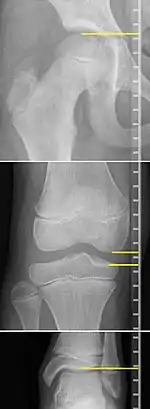

On X-rays, there is generally measurement of both the femur and the tibia, as well as both combined.[4] Various measuring points for these have been suggested, but a functional method is to measure the distances between joint surfaces:[4]

- Femur length: The superior aspect of the femoral head and the distal portion of the medial femoral condyle.

- Tibial length: The medial tibial plateau and the tibial plafond

Clinical measurement of leg length conventionally uses the distance from the anterior superior iliac spine to the medial malleolus.[9] Projectional radiographic measurements of leg length have two main variants:[10]

- Orthoroentgenogram, which takes separate images of the hip, knee and ankle.

On X-rays, the length of the lower limb can be measured from the proximal end of femoral head to the center of the plafond of the distal tibia.[11]